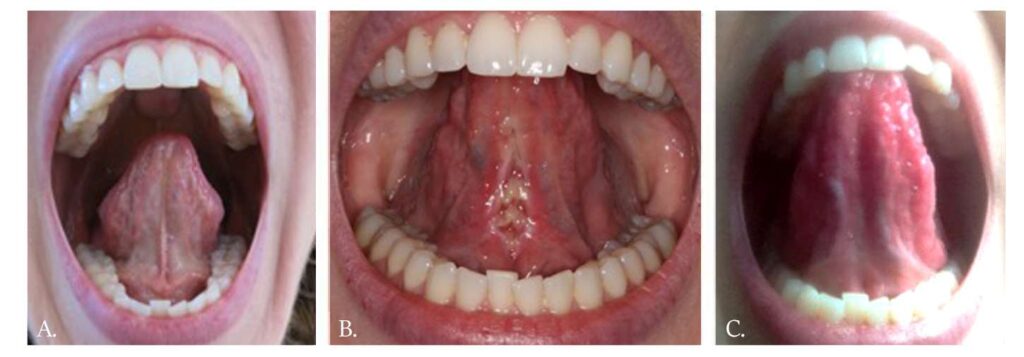

The Tongue-Tie FUNCTIONAL RELEASE is illustrated by clinical cases in Figures 1-3. Note both the immediate and the long-term improved mobility and lift of the tongue. The highly controlled hemorrhage, sealed lymphatics and significantly reduced zone of thermal impact result in less edema and discomfort to the patient. Magnification during the frenectomy is highly recommended as large blood vessels and nerves are in close proximity to the surgical site. Authors prefer to use topical anesthesia to increase the reliability of tongue function during the release. Topical anesthesia does not restrict tongue movement during the procedure when real-time assessment takes place.